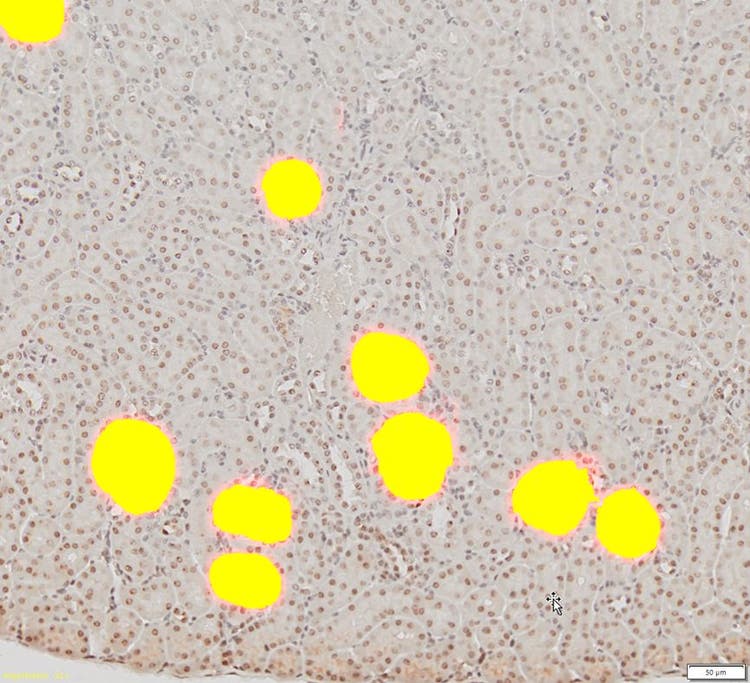

計算されたDNNを他の腎臓画像に適用すると、糸球体が自動的に検出されて、区分されます。

最後に、計算されたDNNを他の腎臓画像に適用すると、糸球体が自動的に検出されて、区分されます。

3. 検出された糸球体をセグメンテーションし、出力画像上で詳細なカウントおよび測定分析の実行に使用できます。

検出された糸球体

TruAI™モジュールによって、既存の自動化方法よりもはるかに高い信頼性と精度で、複雑な画像からの糸球体の検出とセグメンテーションが可能になりました。 カウントや測定などの詳細な分析も、セグメンテーションの結果を基にして実行できます。